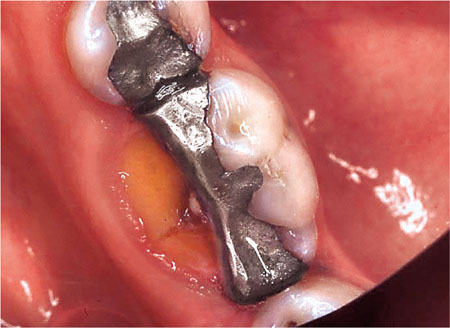

Most indirect restorations are placed to restore the contour, function and appearance of teeth previously restored with plastic restorations. In restoring broken down or damaged teeth with plastic restorations, it is sometimes difficult to achieve appropriate contact areas (Fig 1-1) and occlusal form (Fig 1-2). Indirect restorations such as crowns, onlays and inlays enable the contact areas and the occlusal form to be controlled in the laboratory. The majority of extensive restorations are placed because of primary caries, or caries adjacent to existing restorations. Others will be placed following a fracture of tooth tissue, classically a cusp fracture associated with an occlusoproximal restoration (Fig 1-3). Relatively few extensive restorations are placed as a consequence of trauma.

Fig 1-2 Given the extent of this cavity, it is difficult to place an amalgam restoration with adequate occlusal contour.

Fig 1-3 The MOD restoration in this lower molar tooth, although not large, has weakened the tooth and the lingual cusp has fractured.